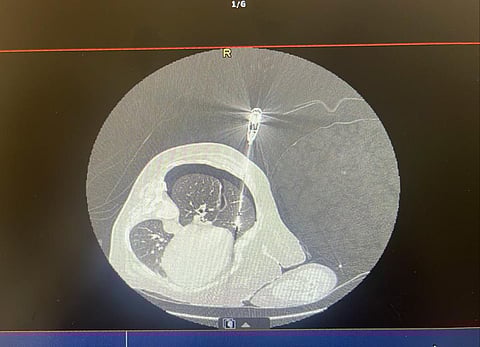

وأجريت العملية على مرحلتين؛ حيث كانت المرحلة الأولى باستخدام تقنية التردد الحراري بإرشاد الأشعة التداخلية لإزالة الأورام الأولية، والمرحلة الثانية باستخدام منظار الصدر الجراحي لاستئصال الأورام المتبقية بالكامل عبر جراحة طفيفة التوغل.